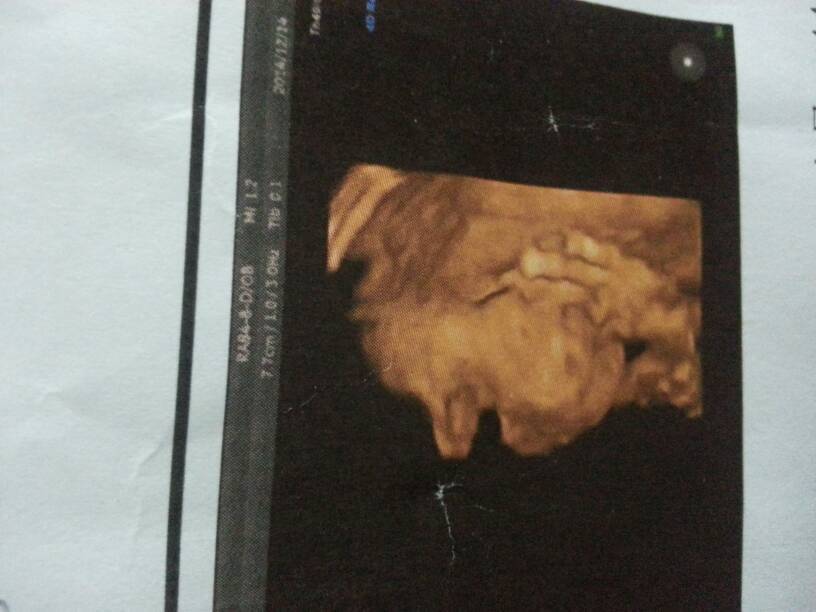

好奇心,会看是男是女的宝妈请帮忙看看吧? 好奇心,会看是男是女的宝妈请帮忙看看吧? 点击展开 最想念的季节wxy 2014-12-30 19:26 为您推荐: 其他回答 看不出来的 159*****361_dml8 2014-12-31 21:44 祝宝妈好孕 爱是习惯i 2014-12-30 22:12 祝宝妈好孕 小昕妈妈 2014-12-30 21:42 看不出来, 小熙熙妈咪 2014-12-30 20:58 看不出来!! 宝宝健康快乐出生 2014-12-30 20:33 加载更多 相关问题 有懂的宝妈来帮我看看是男是女 我1988年2月的宝宝预产期7月12号,有没有会算的宝妈看看是男是女 宝宝出生后第一时间给宝妈说是男是女吗?或者给宝妈先看看吗?